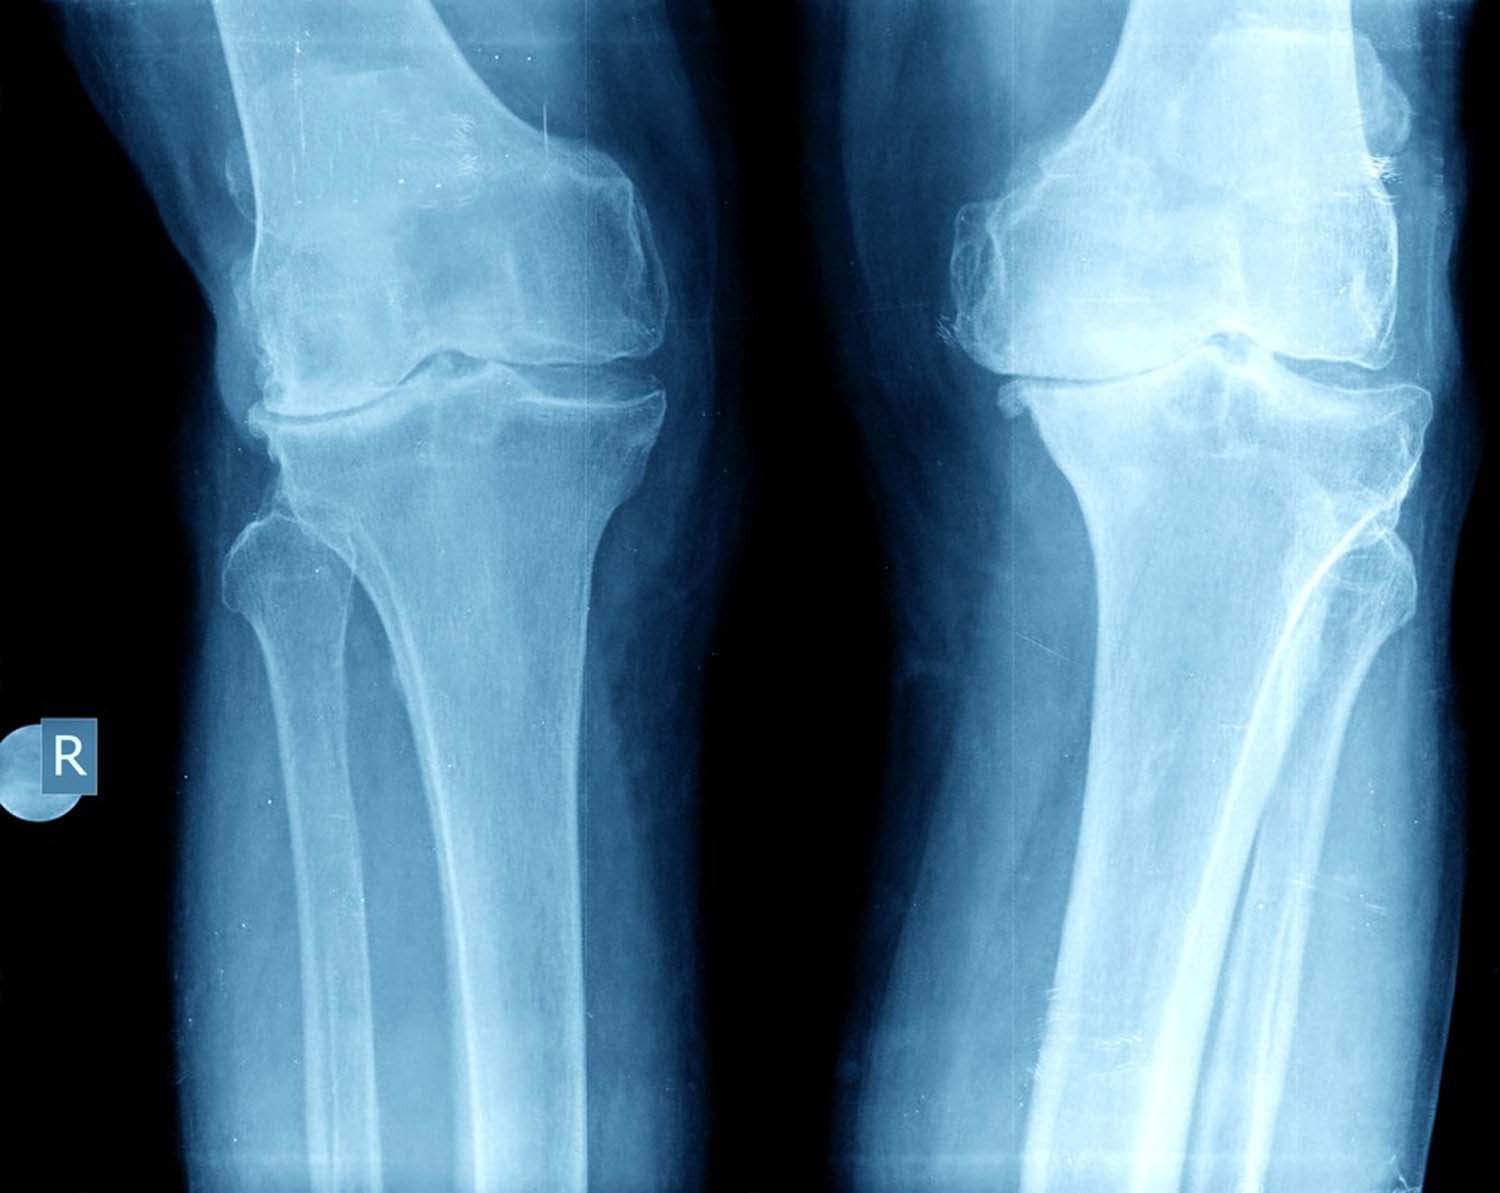

Arthritis of Knee:

Occurs when there is wearing away or destruction of the cartilage either as a degenerative process or an inflammatory or traumatic process.

Types: Osteoarthritis (OA) or Inflammatory arthritis (eg Rheumatoid arthritis RA) or post traumatic arthritis.

In OA of the knee the cartilage wears away leading to the rough bone ends which tend to rub against each other leading to pain and stiffness.

In RA the immune system attacks its own normal tissues (cartilage and ligaments) causing damage. The synovial membrane gets inflamed leading to pain and stiffness.

Post traumatic arthritis occurs when there is cartilage injury after a fracture or due to cartilage damage. It can also occurs after ligament and meniscus injury which lead to instability and further wear of the joint.